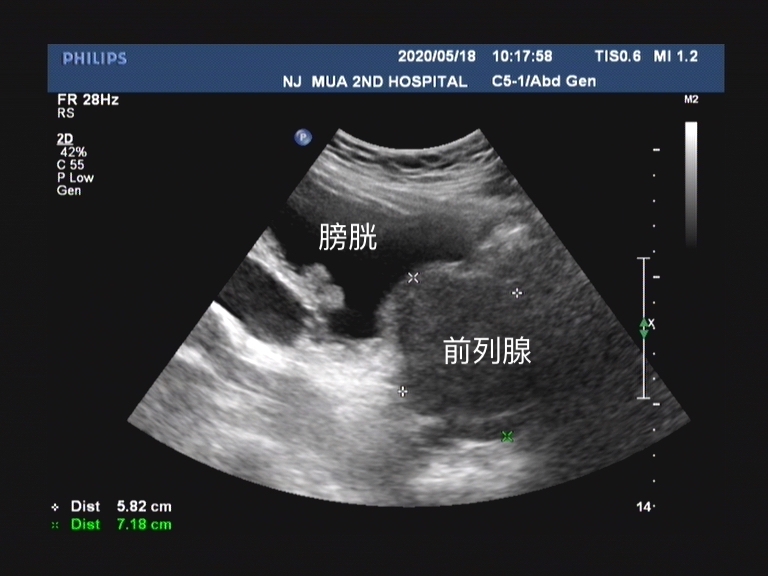

膀胱逼尿肌功能减退,膀胱功能低下不能手术治疗,或经手术治疗后功能仍不能使膀胱排空仍存在较多残余尿的前列腺增生患者,可以中医药疗法为主导。

这部分患者多是已经处 于膀胱的失代偿期 ,划归到前列腺增生的病程中就是已经 处于中晚期的意思 ,这部分患者即使接受手术治疗, 由于膀胱功能已经受损,解除尿路梗阻后仍不能获得有效疗效。 部分研究发现中医药治疗可有效改善患者膀胱活动低下态势, 提高膀胱收缩力 ,认为术后排尿困难的患者可以经过中医药治疗,可以获得良好的临床疗效。